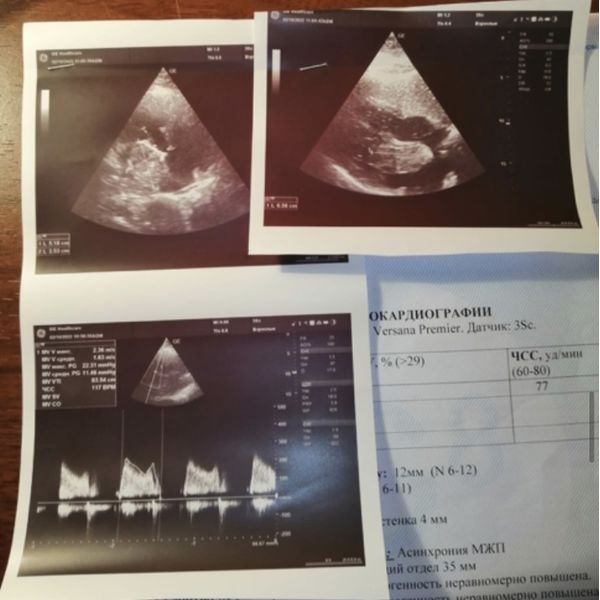

По результатам эхокардиографии:

- конечно-диастолический размер — 44 мм;

- конечно-диастолический объём — 90 мл;

- фракция выброса — 65 %;

- левое предсердие расширено до 47 мм, в его полости объёмное, округлое, подвижное образование (предположительно миксома) размером 65 × 51 × 40 мм, оно фиксировалось к межпредсердной перегородке и имело широкую ножку;

- образование через митральный клапан выпячивалось в полость левого желудочка, чем вызывало тяжёлую обструкцию (непроходимость) клапана.